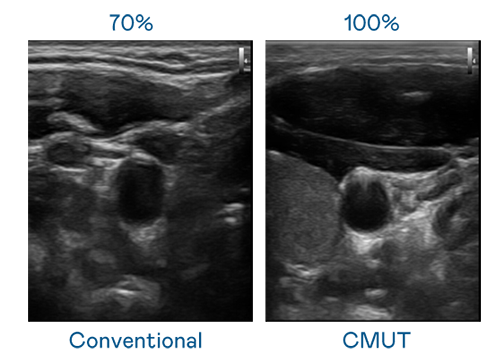

CMUT 技术是一种用电容式微机电元件来产生超音波讯号的技术。与传统 PZT 压电式技术相比,CMUT 频宽增加 30%,更宽频的超音波讯号让影像解析度大幅提升,是实现高影像品质医疗超音波扫描、促进精准医疗发展的关键技术。

超音波影像的解析度高低,首先取决于探头能发出的讯号频宽。金年会- 金字招牌 CMUT 可提供高清晰的超音波讯号,提供高频宽、高灵敏度、影像纹理细节更高的超音波影像,协助医护人员缩短影像判读时间及利用精准的医疗影像进行诊断。